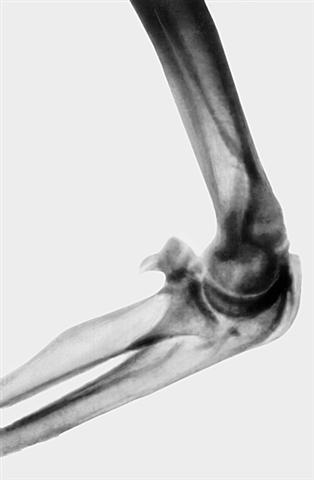

Рис. 13б). Рентгенограмма локтевого сустава при параартикулярной оссификации — боковая проекция.